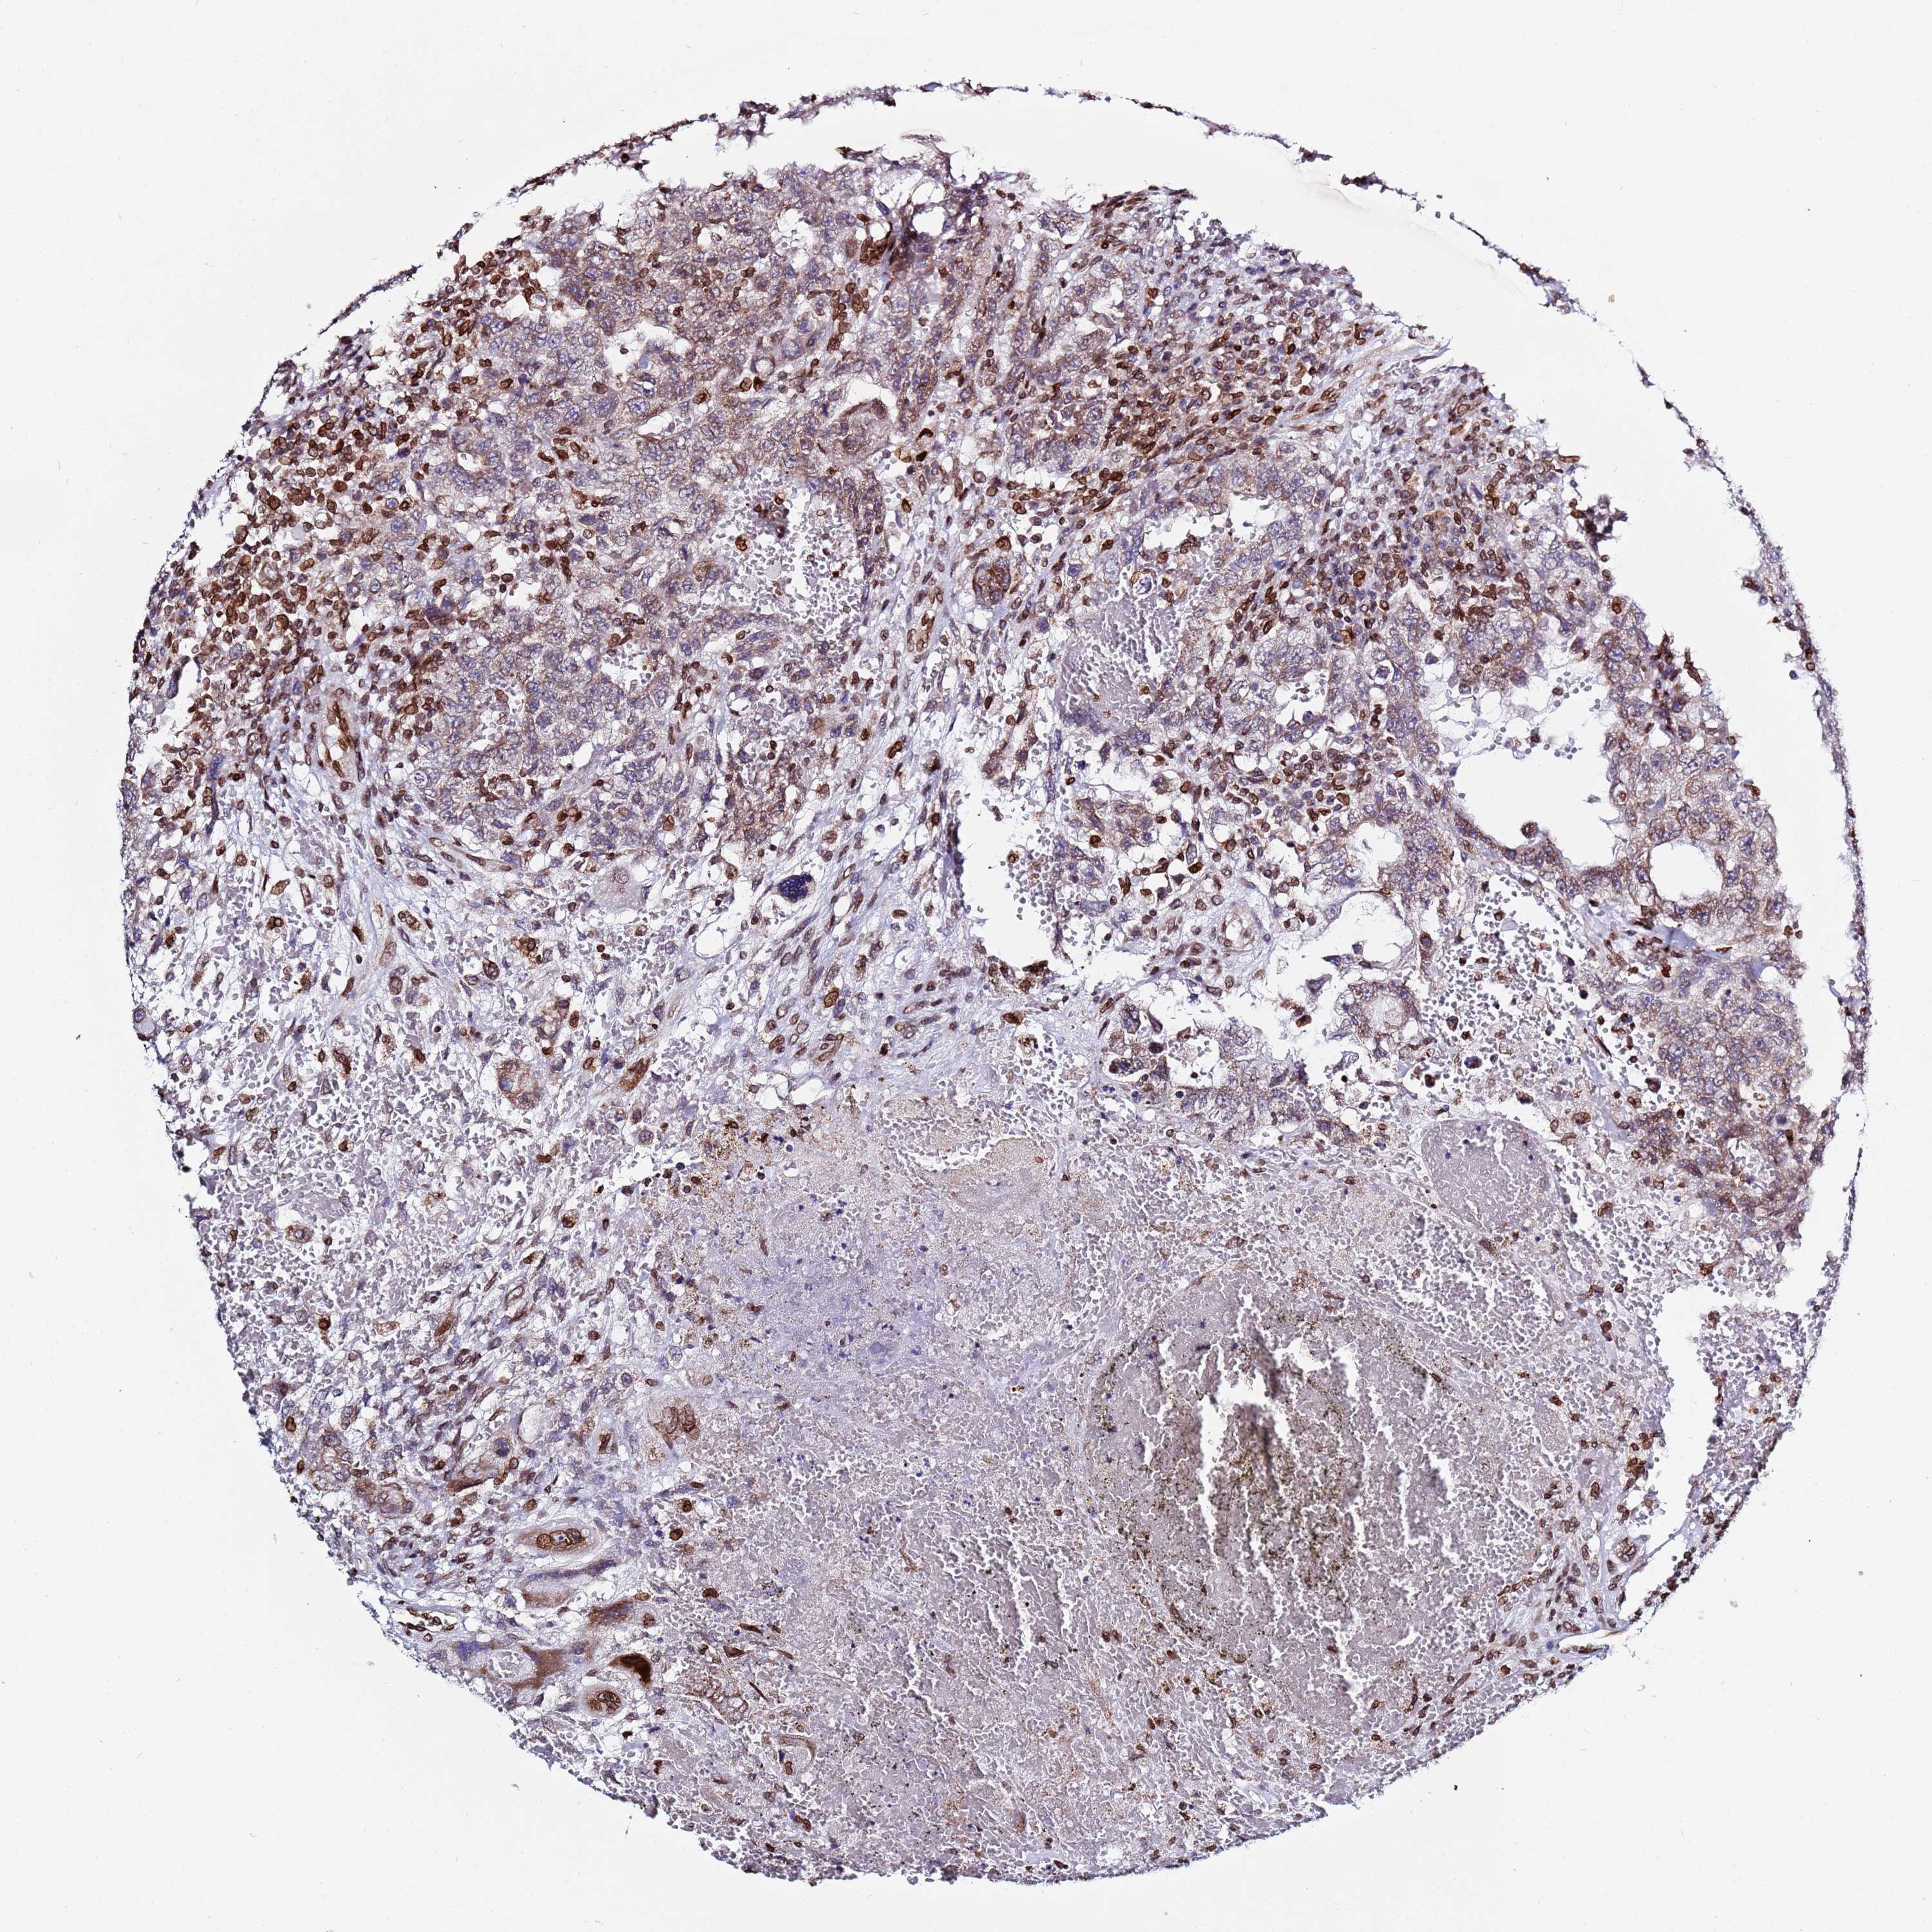

TESTIS CANCER - Protein expressioni

A mouse-over function shows sample information and annotation data. Click on an image to view it in a full screen mode. Samples can be filtered based on level of antibody staining by selecting one or several of the following categories: high, medium, low and not detected. The assay and annotation is described here.

Note that samples used for immunohistochemistry by the Human Protein Atlas do not correspond to samples in the TCGA dataset.

Antibody stainingi

Antibody staining in the annotated cell types in the current human tissue is reported as not detected, low, medium, or high, based on conventional immunohistochemistry profiling in selected tissues. This score is based on the combination of the staining intensity and fraction of stained cells.

Each image is clickable and will lead to virtual microscopy that enables deeper exploration of all samples and also displays staining intensity scores, fraction scores and subcellular localization as well as patient and tissue information for each sample.

Antibody HPA047151

Seminoma, NOS

Carcinoma, Embryonal, NOS